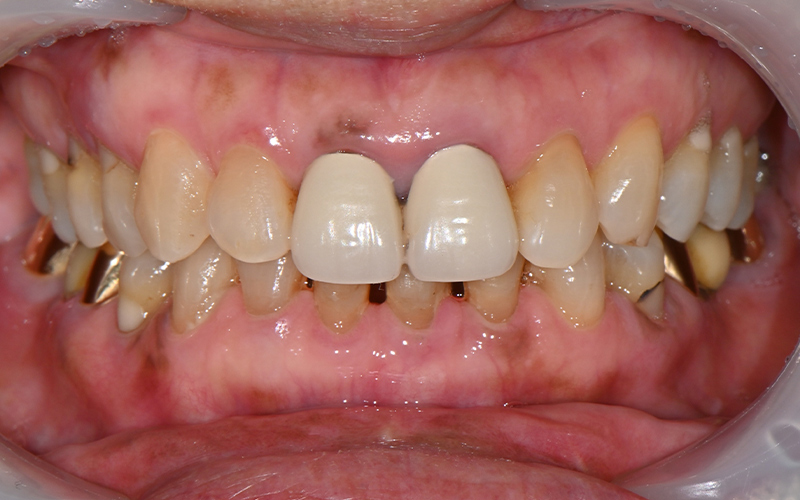

💕 Before > After 💕

![[Seokchon Gobun Station Dental Clinic] When Is an Implant Needed? image 9](https://pub-9f2bb3498faf4d1d8714b41df24753e3.r2.dev/content/clinics/archive/2yawovf9te/naver_blog/qkrgnsdms66403/assets/by_hash/1688f887cd804d08270d31cebd8279ecae6e749cc424634384f57763c04e68de.jpg)

![[Seokchon Gobun Station Dental Clinic] When Is an Implant Needed? image 10](https://pub-9f2bb3498faf4d1d8714b41df24753e3.r2.dev/content/clinics/archive/2yawovf9te/naver_blog/qkrgnsdms66403/assets/by_hash/968c71ff643f8a1c3e670f7ed1468f0668d48268cd8db0febdc090be197a0793.jpg)

2025.02.13 ㅡ> 2025.06.11